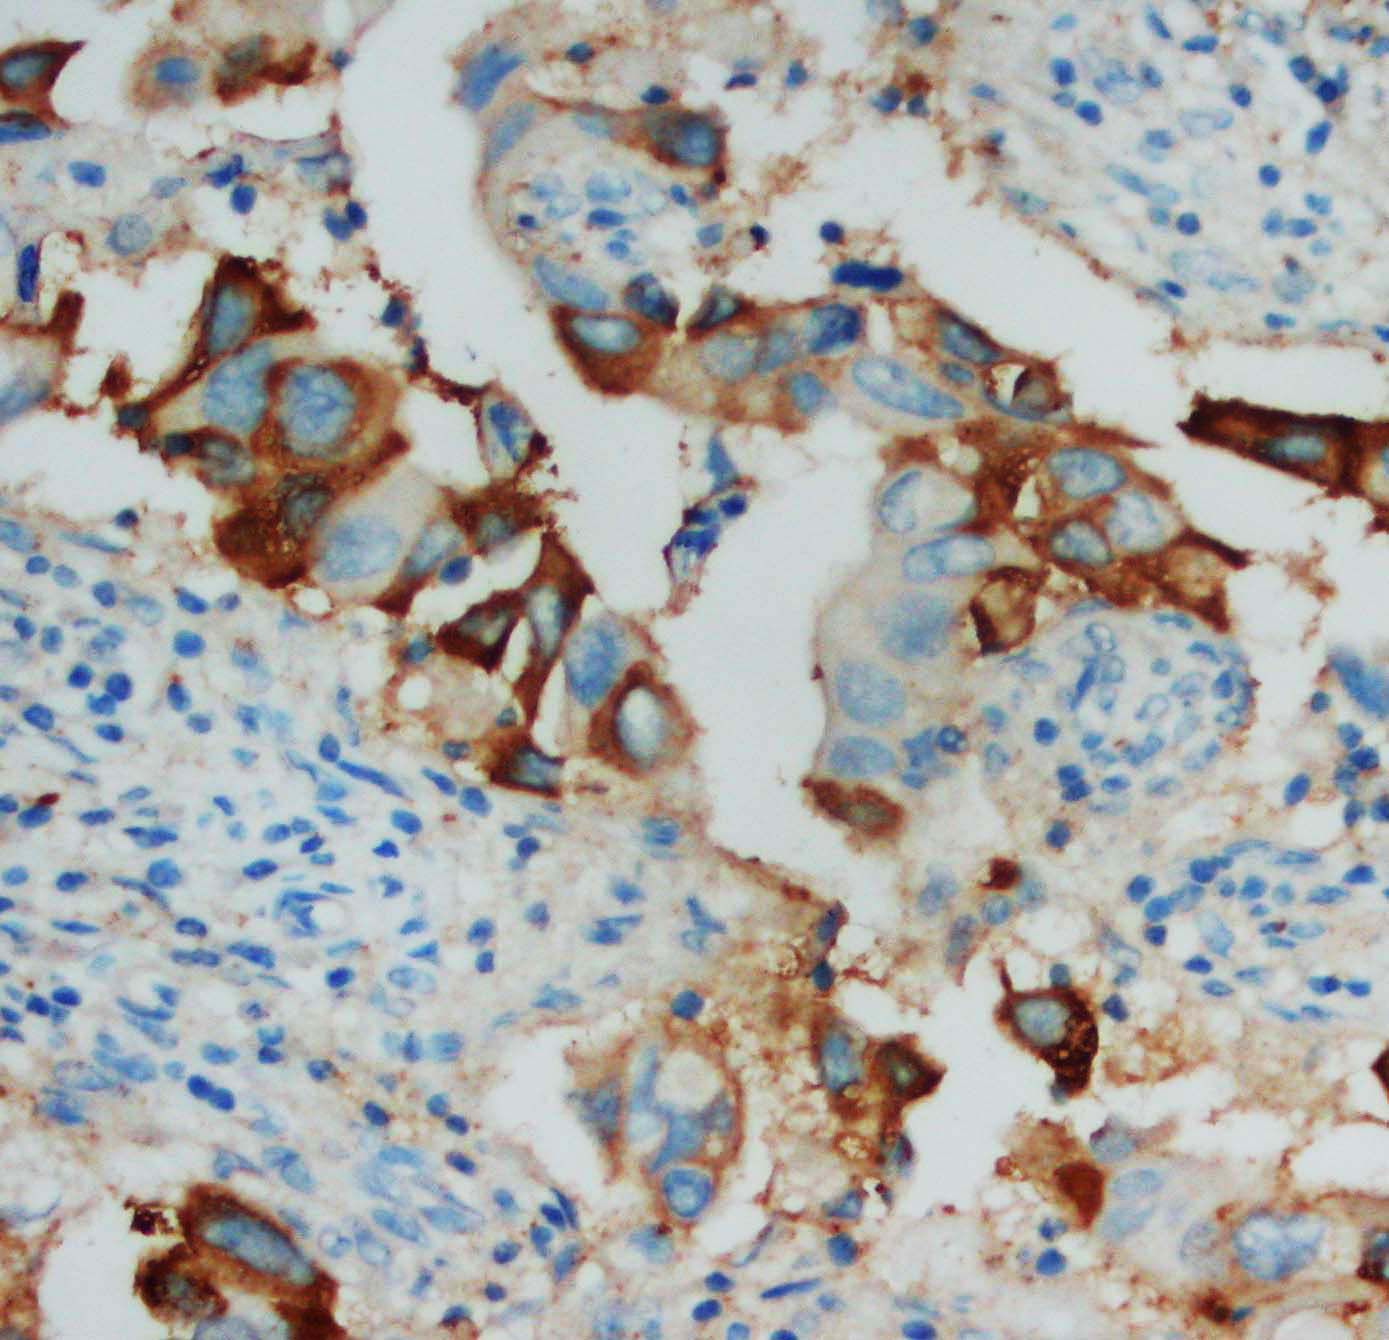

IHC analysis of IL2 using anti-IL2 antibody (BA1644-1).

IL2 was detected in a paraffin-embedded section of human breast cancer tissue. Biotinylated goat anti-rabbit IgG was used as secondary antibody. The tissue section was incubated with rabbit anti-IL2 Antibody (BA1644-1) at a dilution of 1:200 and developed using Strepavidin-Biotin-Complex (SABC) (Catalog # SA1022) with DAB (Catalog # AR1027) as the chromogen.